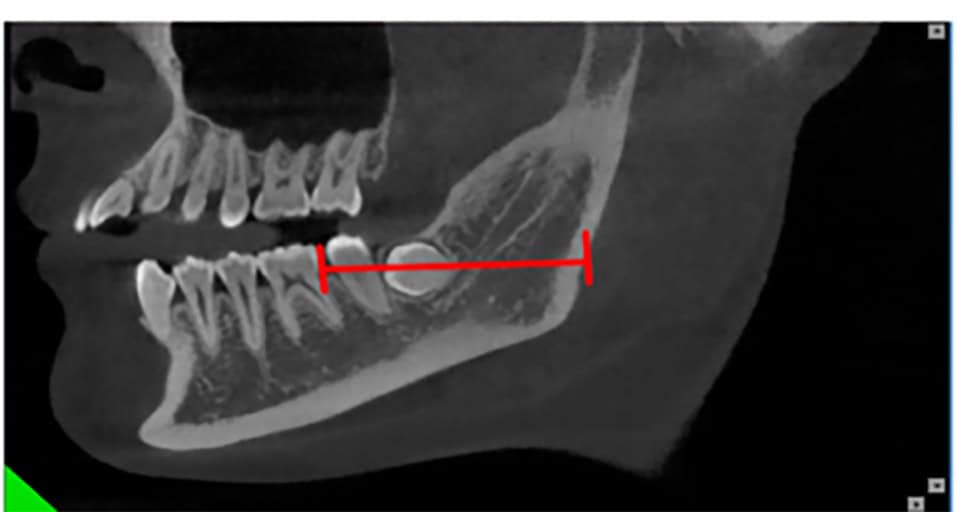

A Cone Beam CT is compiling 3D data, but it still allows us to access it only through 2d representations (slices) in a flat 2D screen. The surgeon has to read these combined 2D images and reconstruct a mental 3D structure of the surgical anatomy, certainly not an easy task to do with precision.

There is only one way and this is training. To maximise the effects of training however and to train others fast and efficiently, you need to leave nothing to chance. The principle strategy is to study carefully the available representations and try and mentally visualize it in advance in 3D. In particular today with the 3D radiographic imaging and tomographies, combined with optical scanning we have some unique representations.

Note here that although the data we aquire from a CBCT are 3-dimensional, in reality the representation is still 2D: we only see it in a flat screen. To recreate a truly 3D representation you will need to 3D print the data from the CBCT. This is actually a very powerfull teaching medium, which we have often utilised in complex surgeries. 3D printing the anatomy prior to surgery allows you to test different techniques and access points with safety, before you choose the best way to go in (or sometimes to not go in at all).

A Challenging surgical case with a complex of vertical and horizontal septa in the posterior sinus. Segmentation of the 3D radiographical and optical data and 3D printing in multiple layers from AMMA Ltd Hong Kong, has allowed for an accurate representation of the anatomy where multiple surgical access approaches were tested.